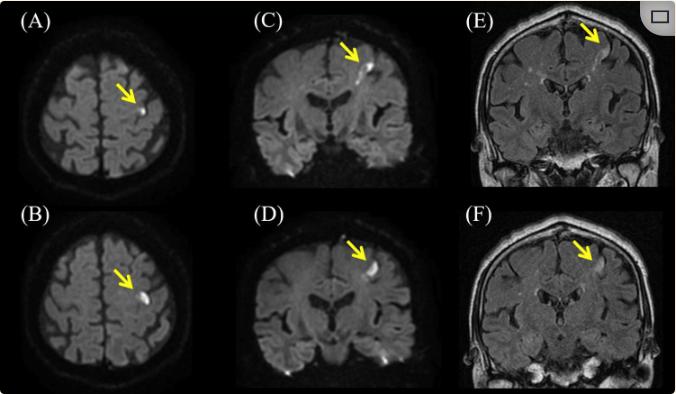

除了轻微升高的C-反应蛋白(0.32 mg/dL)、血糖(118 mg/dL)和γ-谷氨酰转肽酶(75 U/L)外,血液检查并无异常。神经传导研究显示结果正常。扩散加权和T2加权液体衰减反转恢复脑部MRI显示左侧中央前回PK高信号(图1)。脑部磁共振血管造影否认主动脉闭塞。经食管超声心动图显示无血栓、右向左分流或主动脉弓病变。颈动脉超声心动图显示两个眼球上都有斑块,内膜中层厚度(IMT)增厚,但血流速度没有增加(图2)。

图2、颈动脉超声的结果。

颈动脉超声显示双侧颈动脉球的斑块(箭头,此超声图为右侧)